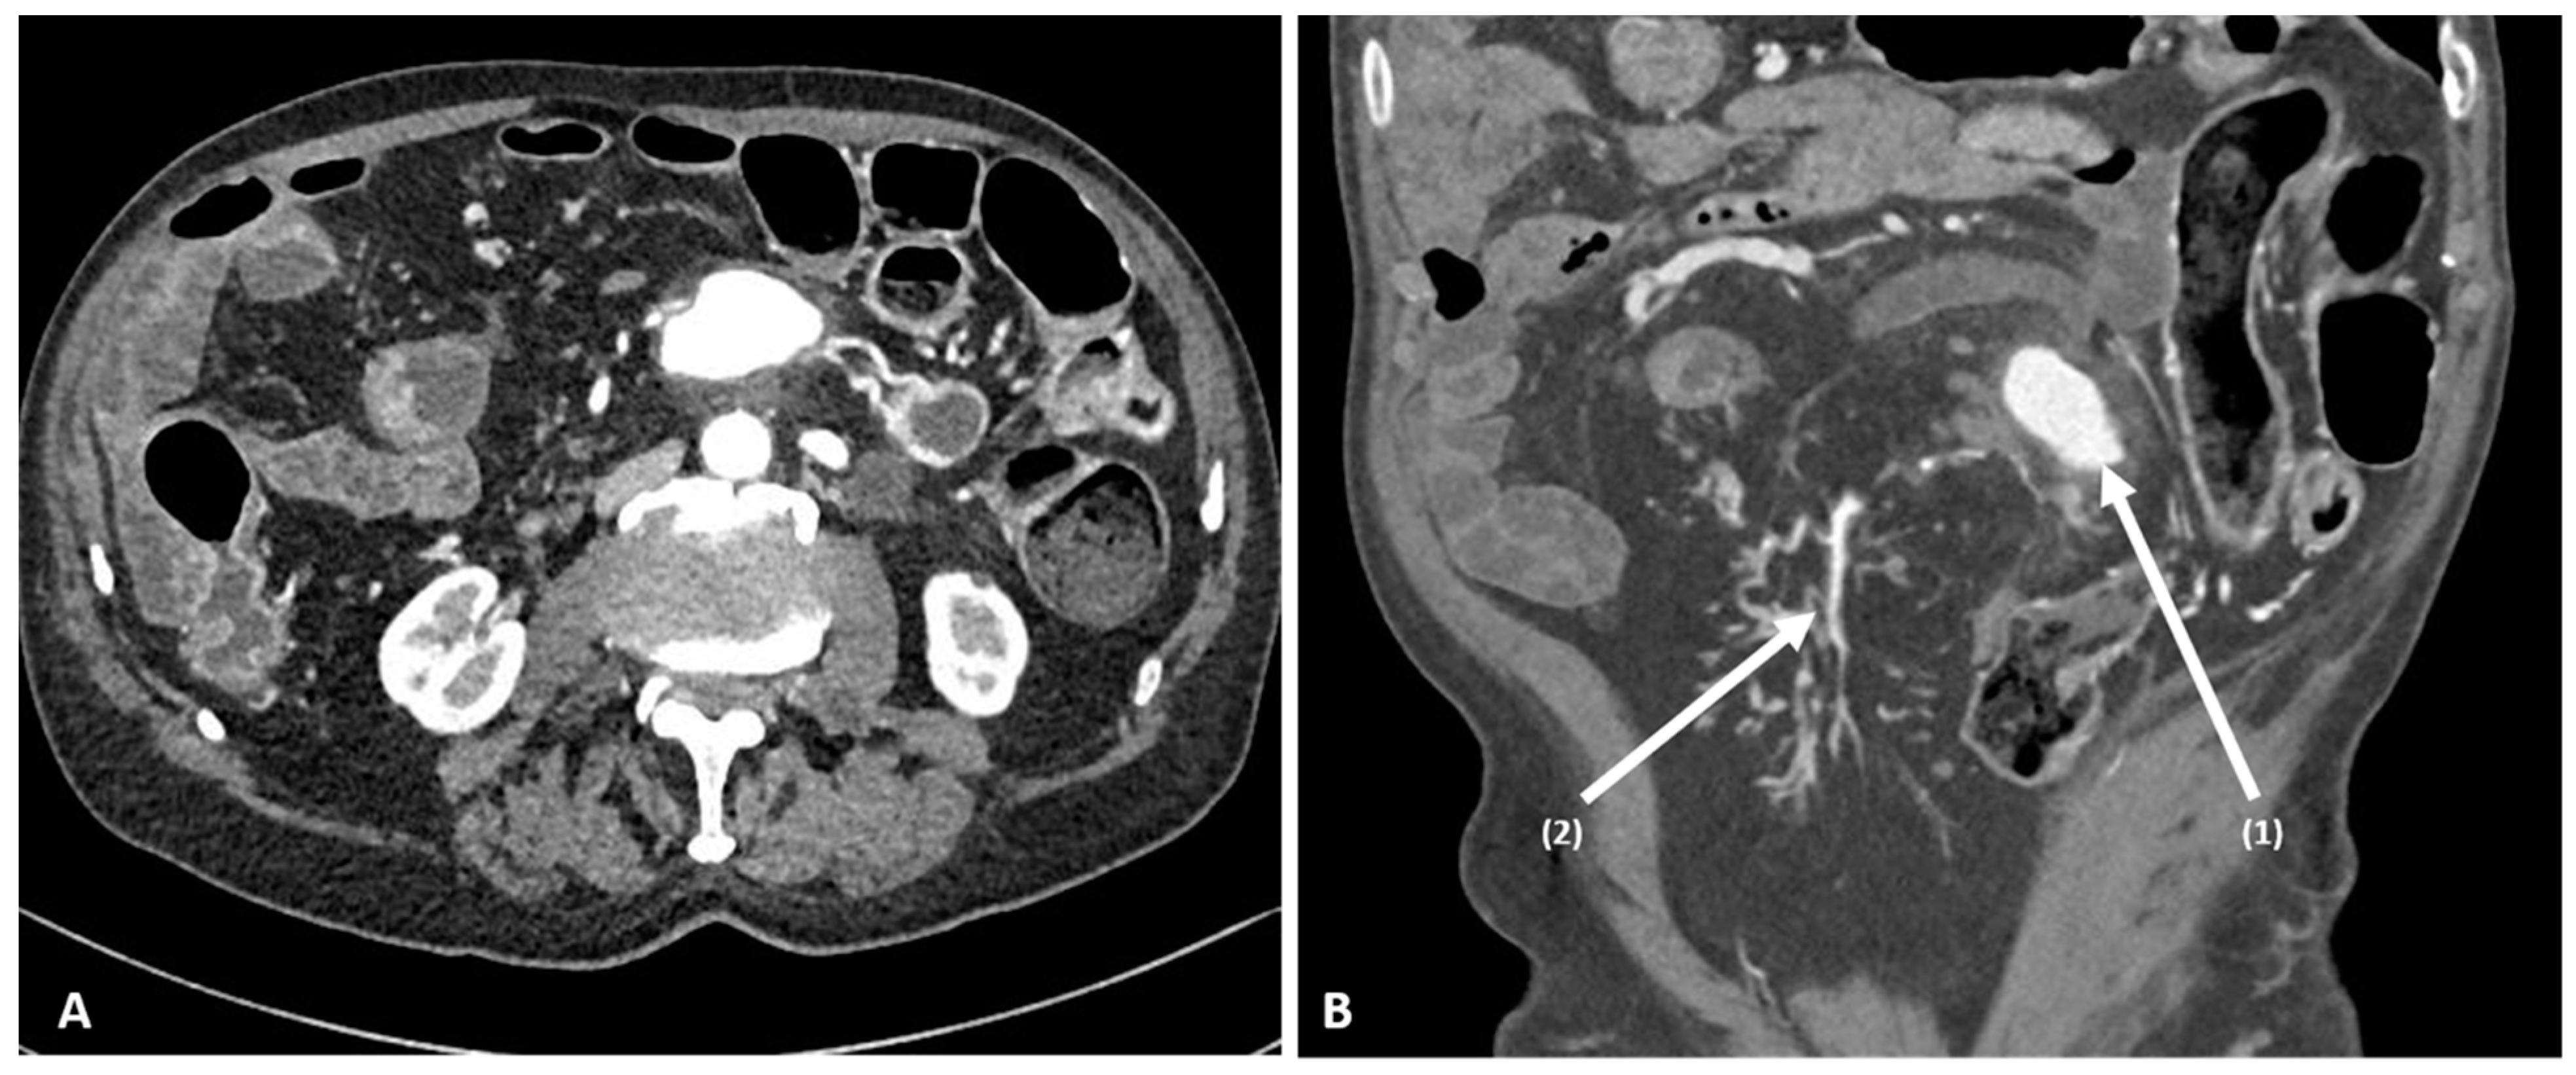

2. Case Report